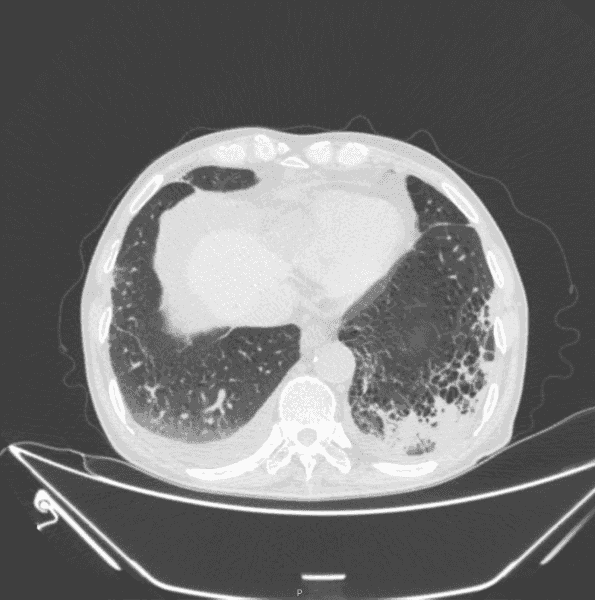

铁蛋白测定: 血清铁蛋白 1242ng/ml。转铁蛋白测定: 血清转铁蛋白 0.663 g/l。胸部 CT: 两肺间质性炎症。两侧少量胸腔积液(图 1)。

图 1:入院第一天胸部 CT,两肺间质性炎症两侧少量胸腔积液咽拭子培养: 未生长致病菌结核菌涂片(痰液): 抗酸染色:阴性细菌涂片(痰液): 革兰染色涂片见 G+球菌、G-球菌各少许血培养(双侧四瓶):。